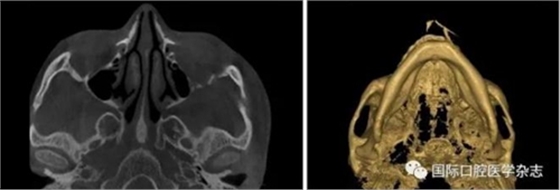

常發(fā)生于20~40歲的人群,病癥常發(fā)生在磨牙后墊區(qū)及頰黏膜,在中國多見于湖南湘潭地區(qū)經常嚼檳榔的人群,長期嚼檳榔,會導致口腔黏膜的纖維性變,失去肌肉的彈性,從而導致張口困難(圖12)。國內外研究證實吸煙也會促進纖維化的發(fā)展。

圖 12 口腔黏膜纖維化